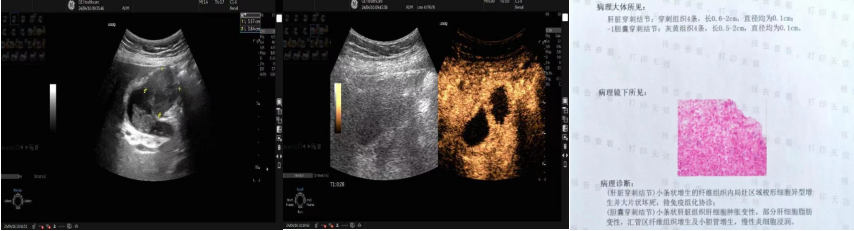

疑似肝脏深部小肿瘤的超声引导下穿刺活检及穿刺病理结果

一名72岁的患者疑似肝脏深部小肿瘤(大小9x8mm),因肿瘤较小,位置较深,且紧贴肝静脉,穿刺难度及风险较高。魏炜教授术前缜密规划穿刺点和穿刺路径,巧妙避开肝内血管,精准取材,病理诊断:肝组织及增生纤维组织内见中分化腺癌浸润转移,结合免疫组化染色结果及病史,考虑胃癌转移可能,为临床的下一步治疗提供可靠的依据。

胆囊超声造影及穿刺病理结果

68岁的阿姨因临床诊断不明确,疑似胆囊肿瘤,难以确定治疗方案。经魏炜教授会诊后倾向于坏死性胆囊炎及邻近肝脏浸润,为明确诊断,魏炜教授在超声引导下对胆囊及邻近肝脏异常回声区进行了精准取材,病理诊断:胆囊穿刺未增生的纤维组织内局灶区域梭形细胞异型增生并大片状坏死;肝脏穿刺为肝脏组织肝细胞肿胀变性,部分肝细胞脂肪变性,汇管区纤维组织增生及小胆管增生,慢性炎细胞浸润;病理结果与超声会诊结果完全一致,展示了魏炜教授丰富的超声诊断经验和精准的判断力,提高了临床超声诊断的符合率,获得了临床和患者的信任。